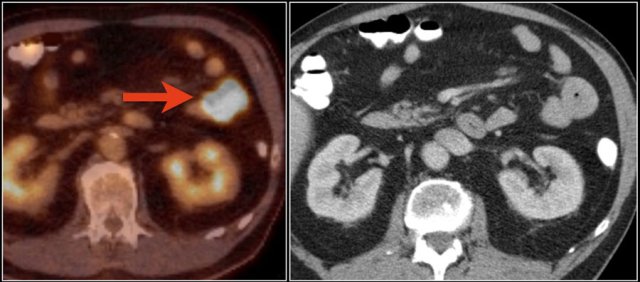

Top images show a circular mass in the proximal jejunum with FDG uptake (yellow arrows).

Lower MR-images show the same jejunal mass with shouldered borders and mesenteric lymphadenopathy (red arrows), consistent with adenocarcinoma.

Here a typical lymphoma presenting as a large thick walled mass in the proximal jejunum with FDG uptake.

Dilated lumen at the site of the mass and prestenotic dilatation of the duodenum (red arrow)